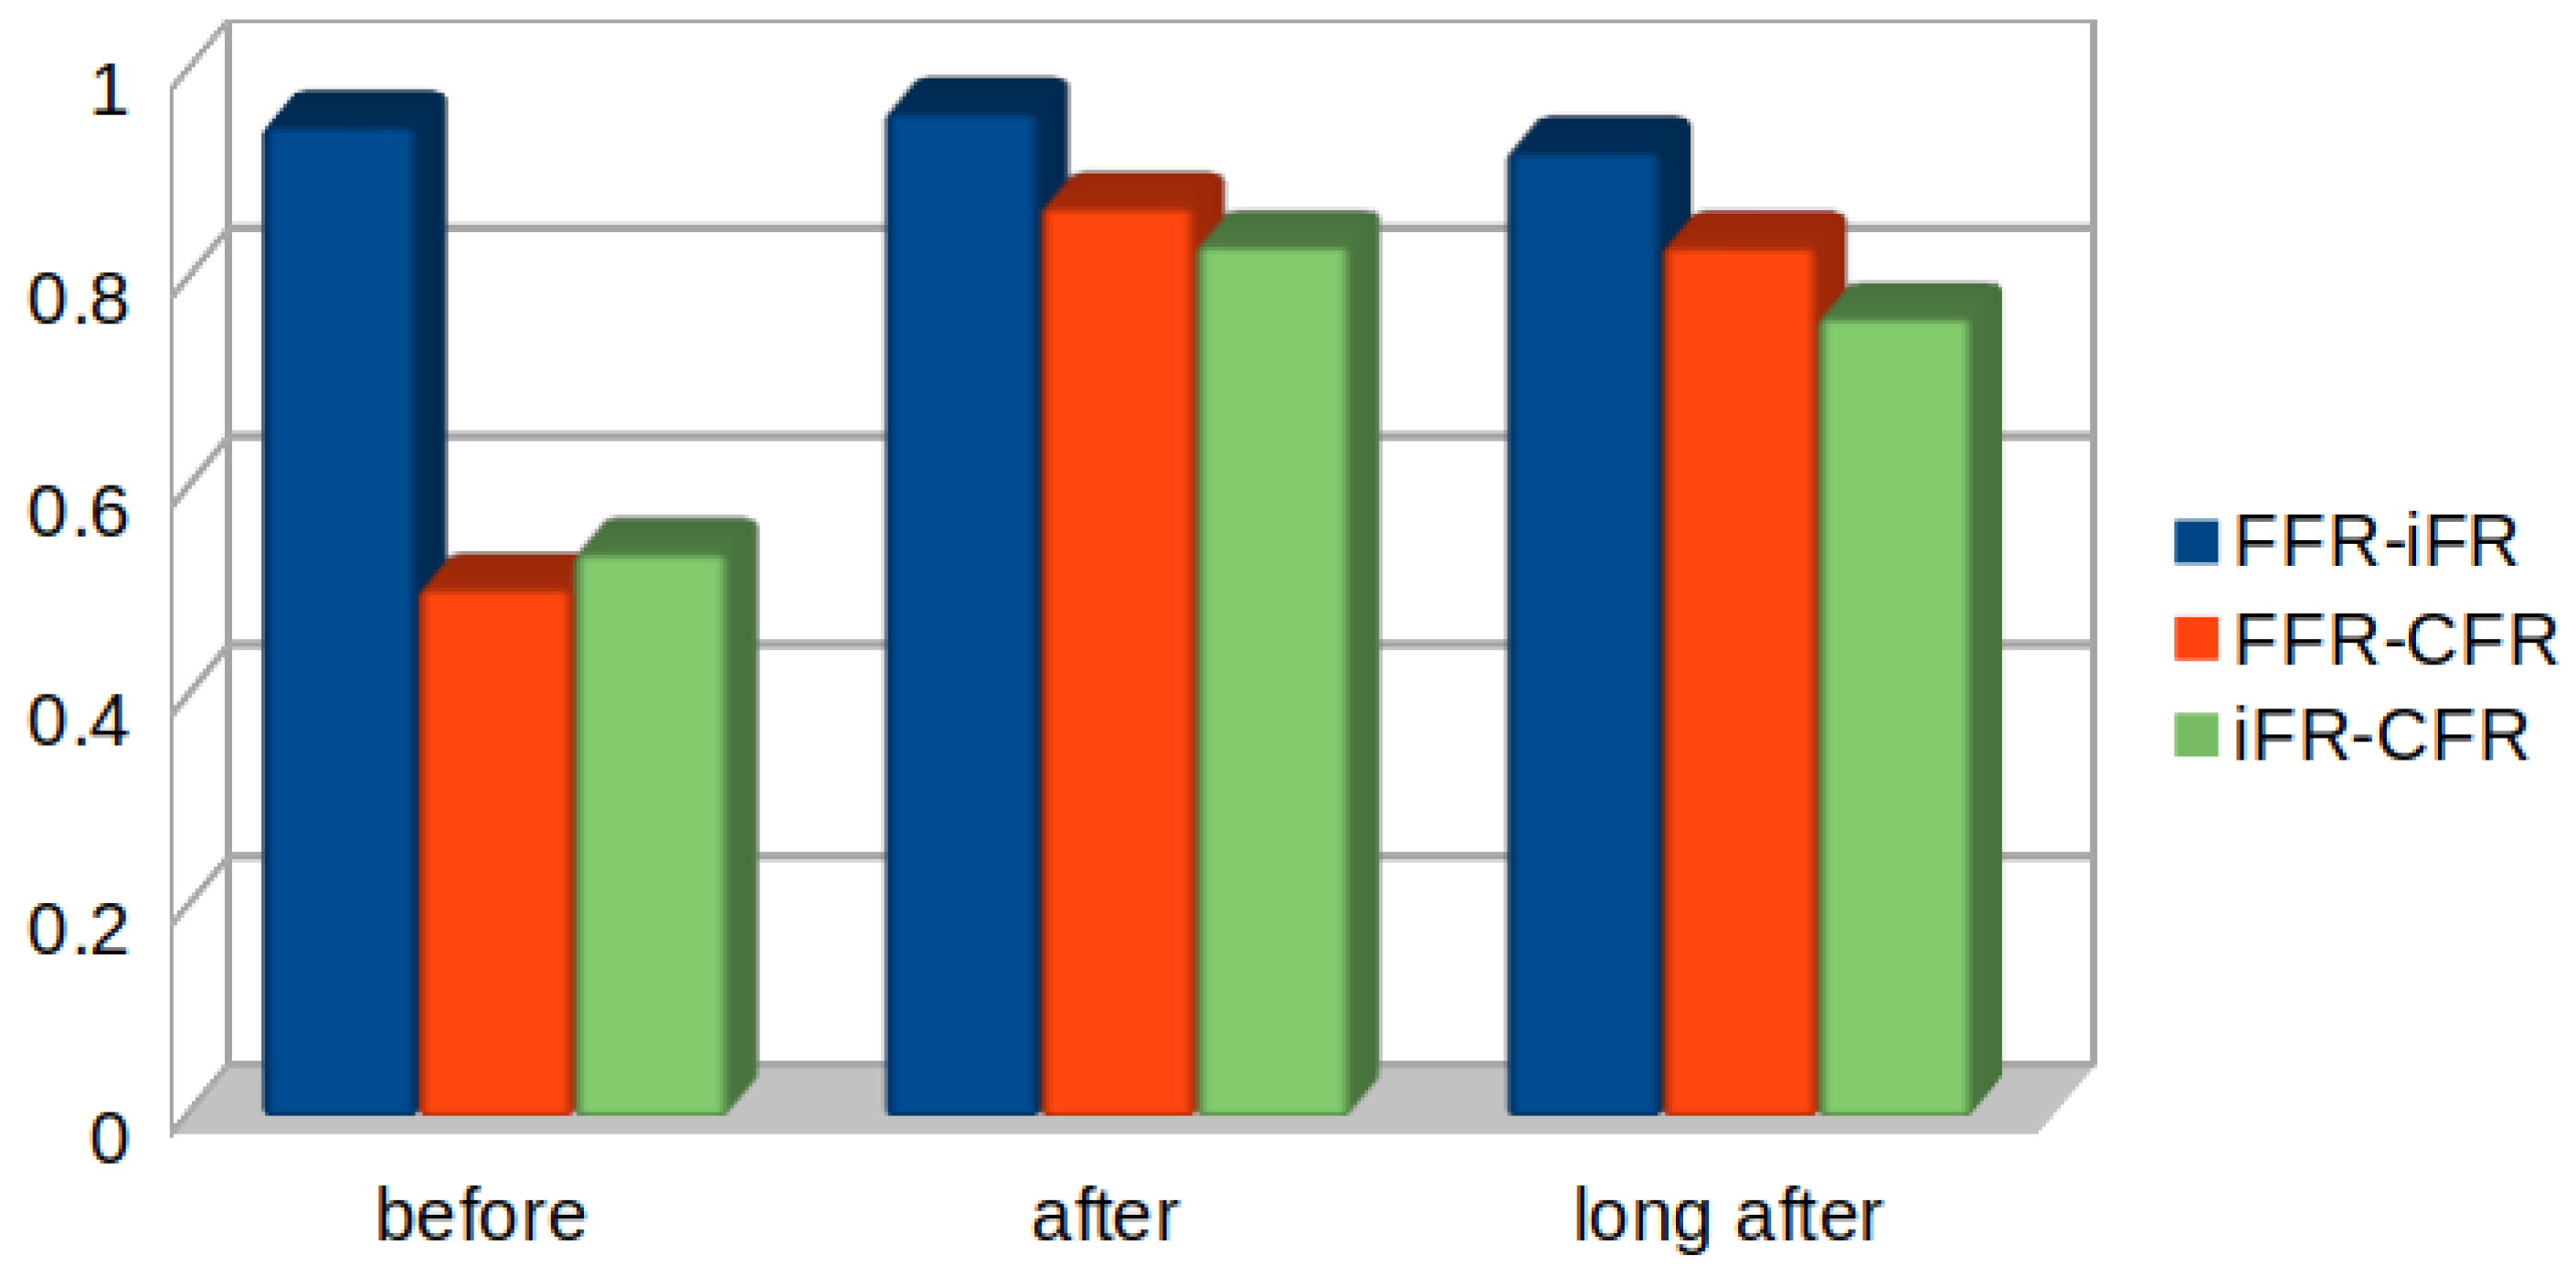

4. Results

5. Discussion